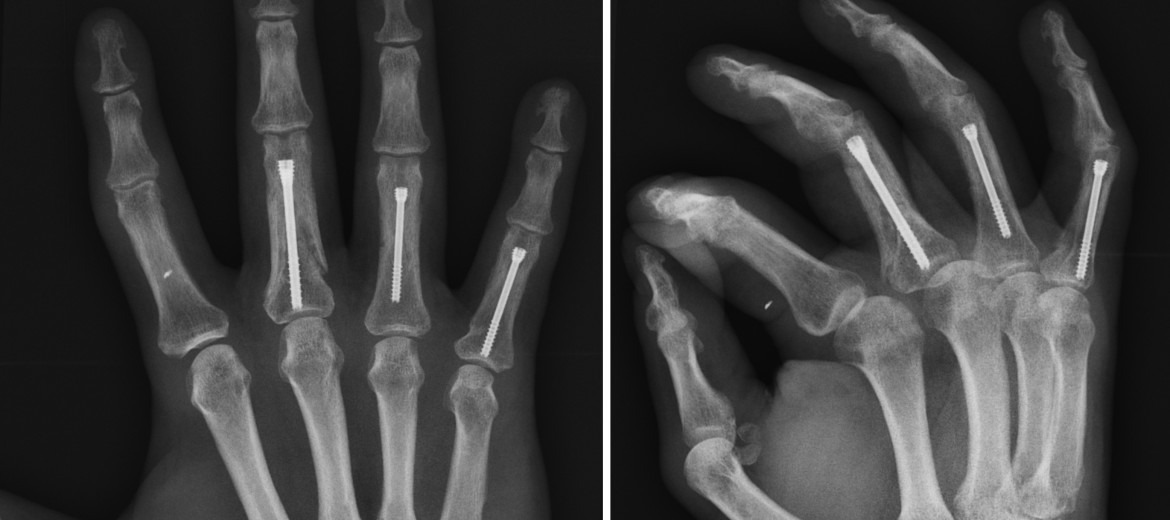

- 개방적 정복 및 내고정(ORIF): 파편이 많거나 관절 간격이 넓을 때 핀·스크루·플레이트 사용.